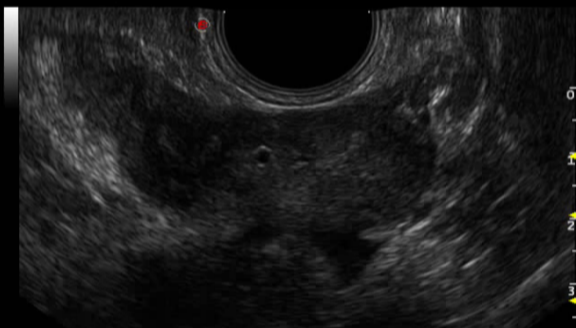

双平面腔内探头:

1.凸阵-线阵组合,微凸探头大角度可视范围

2.微凸探头扫查频率:3-13MH,线阵探头扫查频率:3-13MHz

3.穿刺架应用:经会阴前列腺穿刺(有效避免经直肠穿刺所致出血及感染等风险)

4.临床应用:泌尿科、肛肠科、介入科等

5.泌尿科应用:前列腺检查及穿刺活检,放射粒子植入。

双平面探头